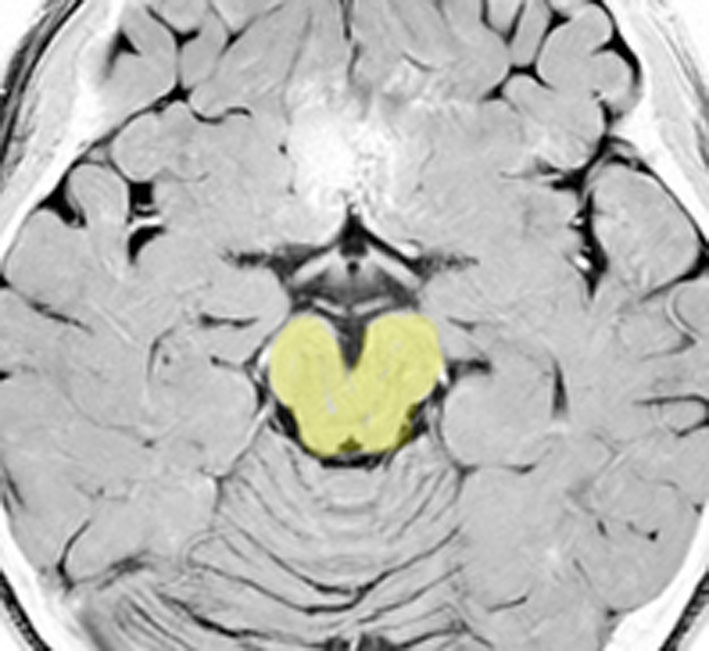

これは脳の中心部を縦切りにした写真です。脳幹部は上から順に,中脳 midbrain (黄色),橋 pons(オレンジ),延髄 medulla oblongata(ピンク)と呼ばれます。

共通しているのは脳幹部の障害では意識障害が出ることです。中脳脚から延髄腹側まで錐体路という運動神経を司る経路があり,これが障害されると片麻痺や四肢麻痺がでます。脊髄視床路の障害では全身の感覚障害となります。主として背側損傷では運動失調も出ます。脳神経麻痺,眼球運動障害,嘔吐などさまざまで複雑な症候が出る重要な部位です。